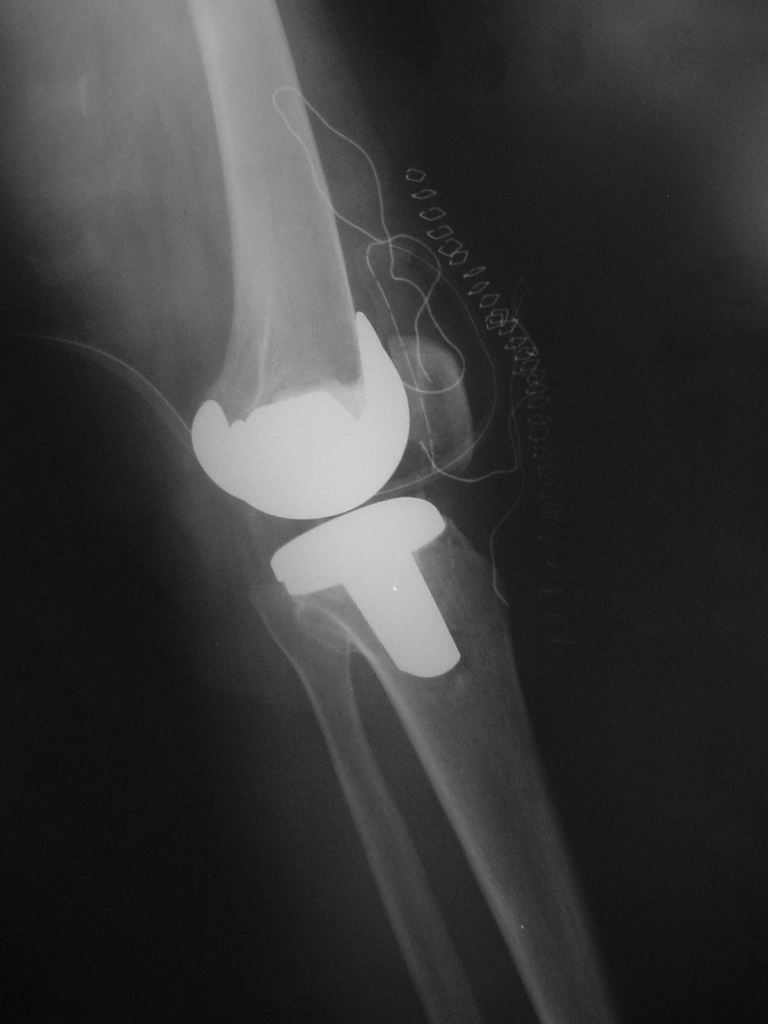

Total Diz Protez ameliyatı kliniğimizde endikasyon dahiline her yaşa başarı ile uygulanmaktadır. Örnek olgumuz: